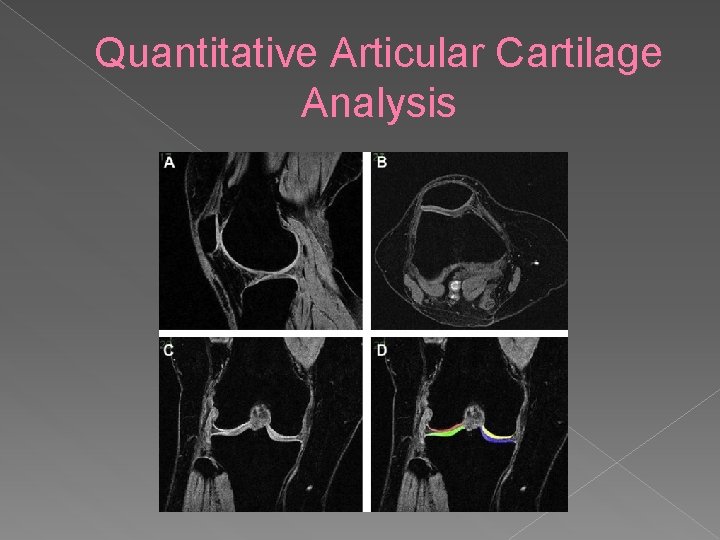

Quantitative Articular Cartilage Analysis High- resolution 3 D imaging sequences • Requires segmentation of the hyaline cartilage • Allows measure of tissue dimensions: • › › Cartilage Volume (VC) Cartilage Area (AC) Area of Subchondral Bone (t. AB) Area of denuded Subchondral Bone (d. AB)

Quantitative Articular Cartilage Analysis

Quantitative Articular Cartilage Analysis Interesting research tool • Quantitative nature makes it powerful • Found associations between: • › Weight gain and increased cartilage loss › Weight loss and decreased cartilage loss › High BMI/Leptin levels associated with cartilage loss › Systemic bone/subchondral bone density and risk of progression